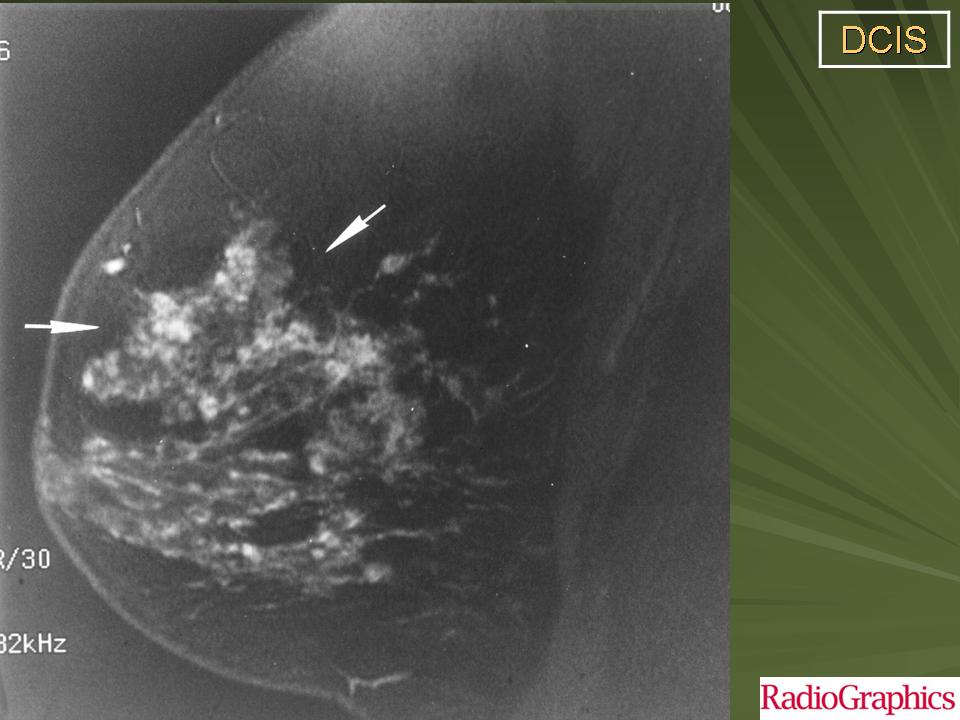

Обычно, ПКИС никак не проявляется и не выявляется при физикальном исследовании. Однако у небольшого числа женщин может отмечаться опухолевидное образование либо какие-то выделения из соска. Чаще всего протоковая карцинома выявляется на маммографии. Дело в том, что «старые» раковые клетки отмирая, не успевают полностью утилизироваться. В результате этого эта область пропитывается солями кальция (так называемое обызвествление) – образуются микрокальцинаты. Эти микрокальцинаты как раз и выявляются на маммограмме. В случае если полученные результаты маммографии врач считает подозрительными на рак, проводится следующий этап диагностики – биопсия.

Часто на маммограммах в области опухоли выявляются микрокальцинаты, что связано с том, что в опухоли происходит омертвление ее клеток (некроз), которые в последствие пропитываются солями кальция. Опухоль при инвазивной карциноме может быть различных размеров, и у клеток может быть различное время деления, так что некоторые клетки растут быстрее других.